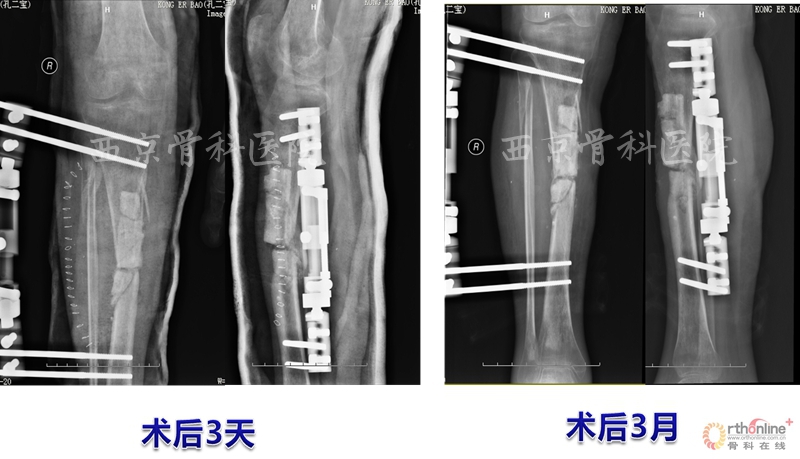

术后,他们按照组织工程再生骨临床转化应用方案定期进行血液指标、免疫指标和影像学指标的检测复查,患者术后3个月即可扶拐下地行走,术后6个月可弃拐逐步下地负重行走,12个月拆除已使用了2年的外固定支架,行走及下肢关节活动如常,恢复了正常的生活与劳动能力。